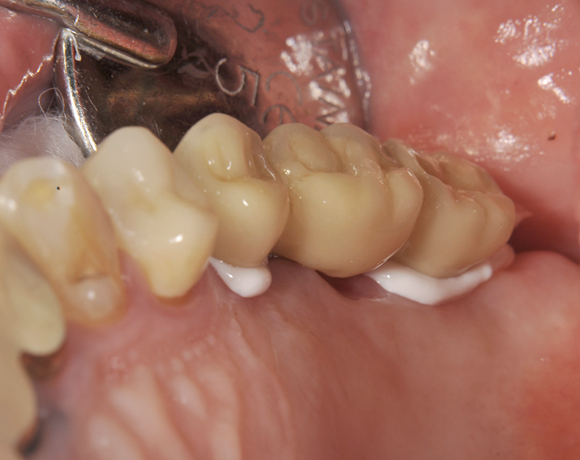

Im vorliegenden Patientenfall wurden für die Zähne 25 und 27 jeweils ein Implantat gesetzt. Nachdem die Implantate eingeheilt waren, wurde 25 – 27 mit einer Brücke versorgt.

Der prothetische Teil